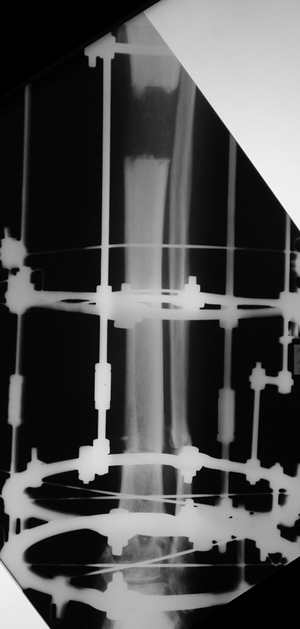

Женщина 46 лет, неудачно лечившаяся по поводу перелома голени в нижней 1\3 сначала в гипсе, поступила через 6 месяцев после остеосинтеза пластиной (рис 1). Имелась деформация в нижней 1\3 голени: варус, антекурвация, наружная ротация, два свища. Удалена пластина, дебридмент мягких тканей,

остеотомия м\б кости, аппарат Илизарова. По рентгенограммам в двух проекциях произведено планирование устранения смещений (рис 2 и 3), между вторым и третьим кольцом установлены 6 телескопических дистракторов Гесапода, данные введены в программу, и далее втечение 10 дней больная подкручивала телескопы согласно выданной компьютером инструкции. По завершению репозиции гексаподные телескопы обратно заменены на обычные штанги от аппарата Илизарова (рис 4 и 5). Еще через две недели забит гвоздь (рис 6, контроль

через 4 месяца).